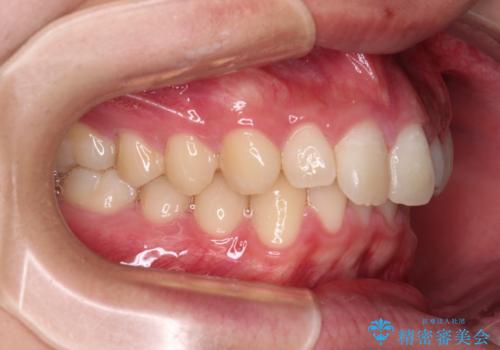

下顎前歯が一本欠損しており、下顎の歯列が小さいため、ディープバイトになりやすい状態でした。

傾斜しいている大臼歯を立ち上げながら、下顎歯列を上顎に対して前方位となるように工夫し、デコボコを解消した上でディープバイトも改善することができました。